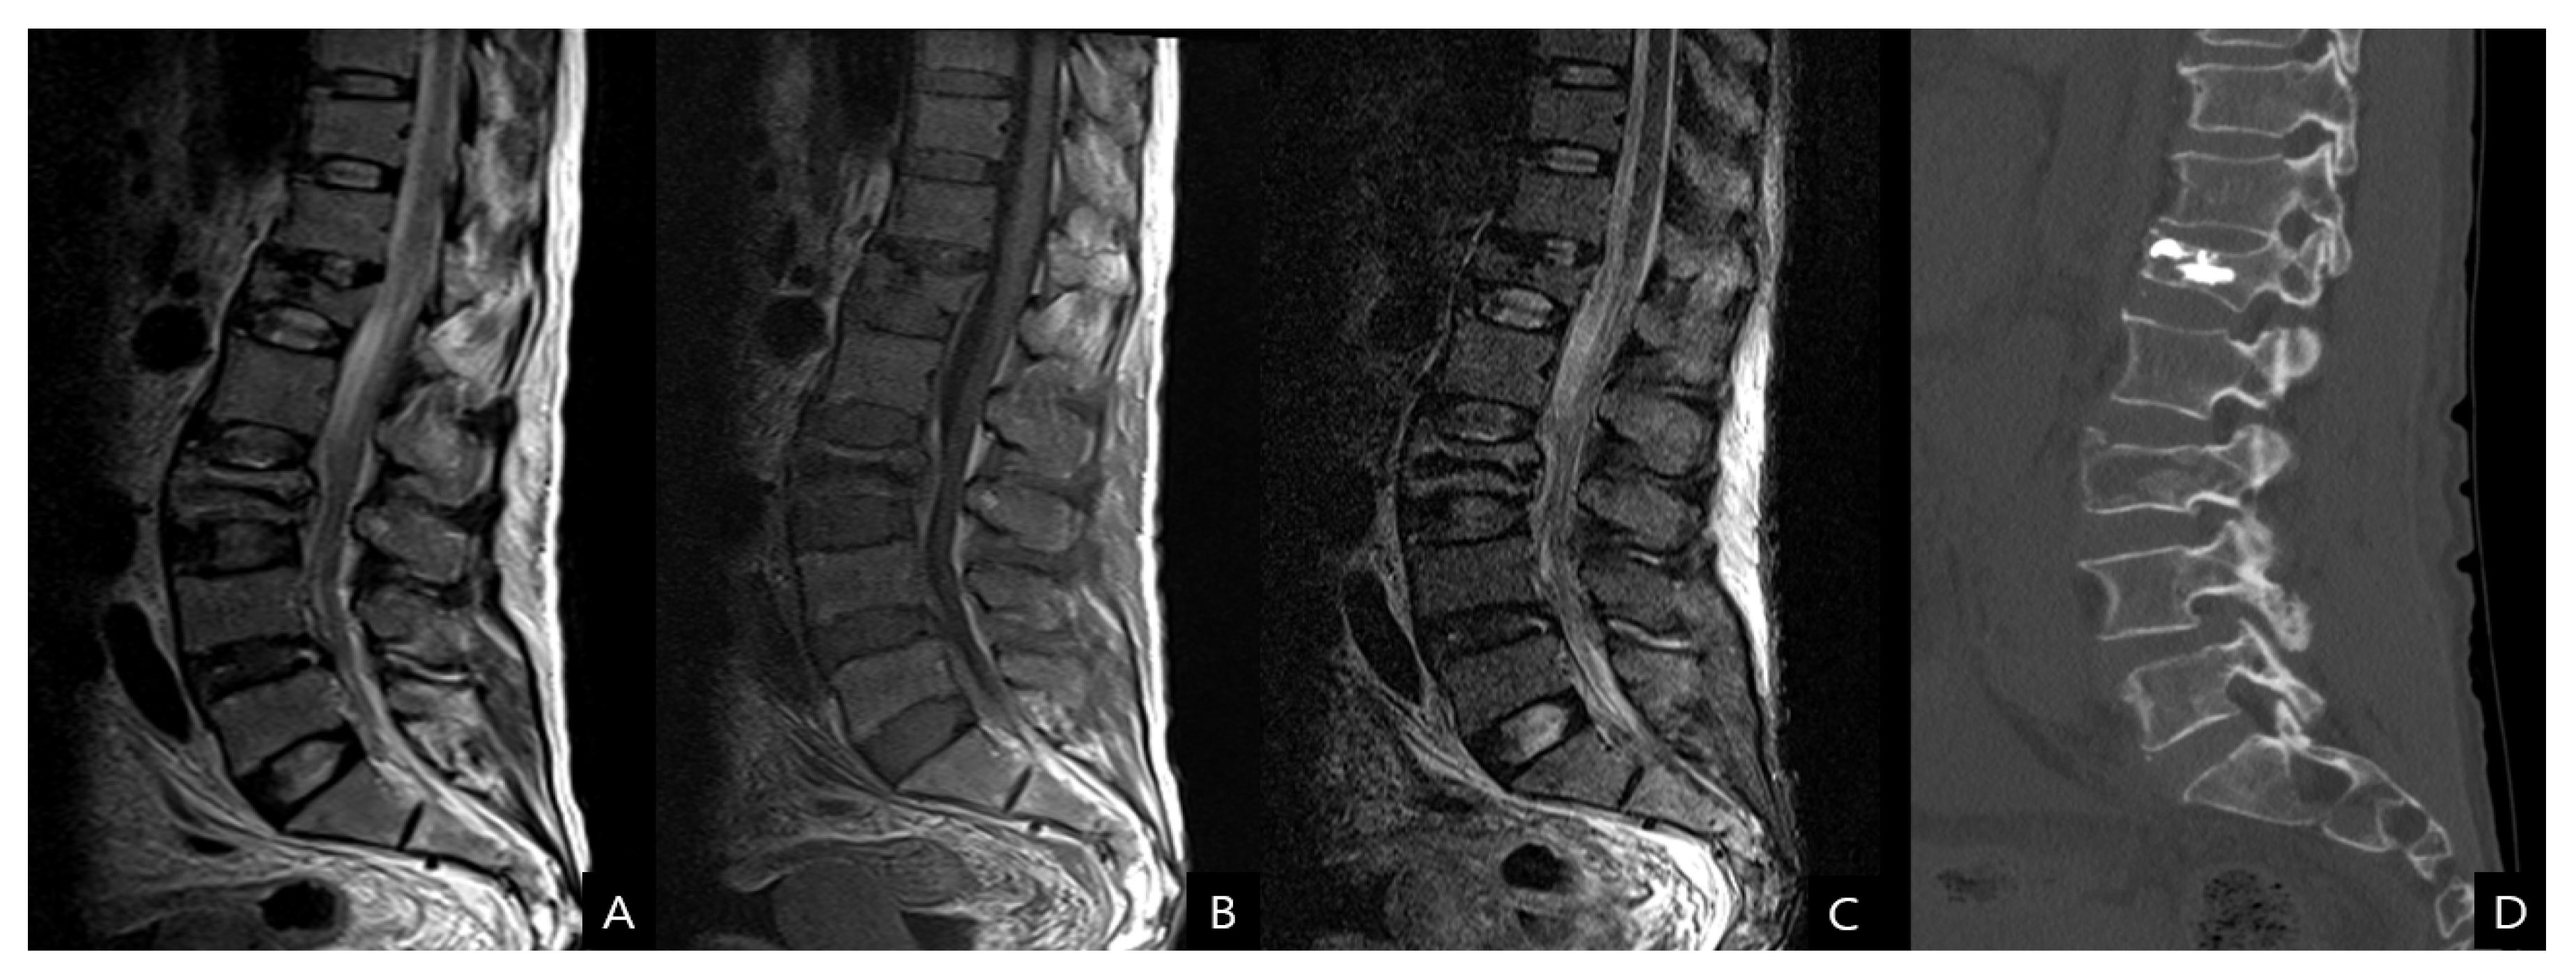

Figure 2.

(A) T2-weighted, (B) T1-weighted, (C) short tau inversion recovery magnetic resonance images and also (D) computed tomography scan show a stable-type osteoporotic VCF at L3.